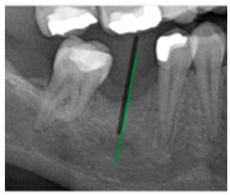

3.3. Comparison with Clinical Ground Truth and AI-Assisted Framework

This subsection presents a comparison between the dentist-defined clinical gold standard and the predictions generated by our AI-assisted framework to evaluate the reliability of implant pathway orientation. The result is shown in Table 10, the preserved DPR validation set was used for verification, and the AI-assisted framework results were overlaid onto the original DPR images to provide a clear visualization. The AI-assisted framework pathways (green lines) were highly consistent with the dentists’ ground-truth annotations (black lines). Quantitatively, the mean squared error (MSE) between the predicted implant direction and the dentists’ planned results was only 1.537° across multiple test images. This minimal deviation validates the proposed system’s technical feasibility. It highlights its clinical potential to provide accurate and stable guidance for implant placement, thereby reducing the risk of misalignment and supporting efficient preoperative orientation.

Comparison between model-predicted pathways and dentist-planned pathways.